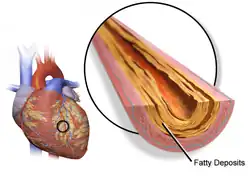

HRT with estrogen and progesterone also improves cholesterol levels. With menopause, HDL decreases, while LDL, triglycerides and lipoprotein a increase, patterns that reverse with estrogen. Beyond this, HRT improves heart contraction, coronary blood flow, sugar metabolism, and decreases platelet aggregation and plaque formation. HRT may promote reverse cholesterol transport through induction of cholesterol ABC transporters.[43] Atherosclerosis imaging trials show that HRT decreases the formation of new vascular lesions, but does not reverse the progression of existing lesions.[44] HRT also results in a large reduction in the pro-thrombotic lipoprotein a.[45]